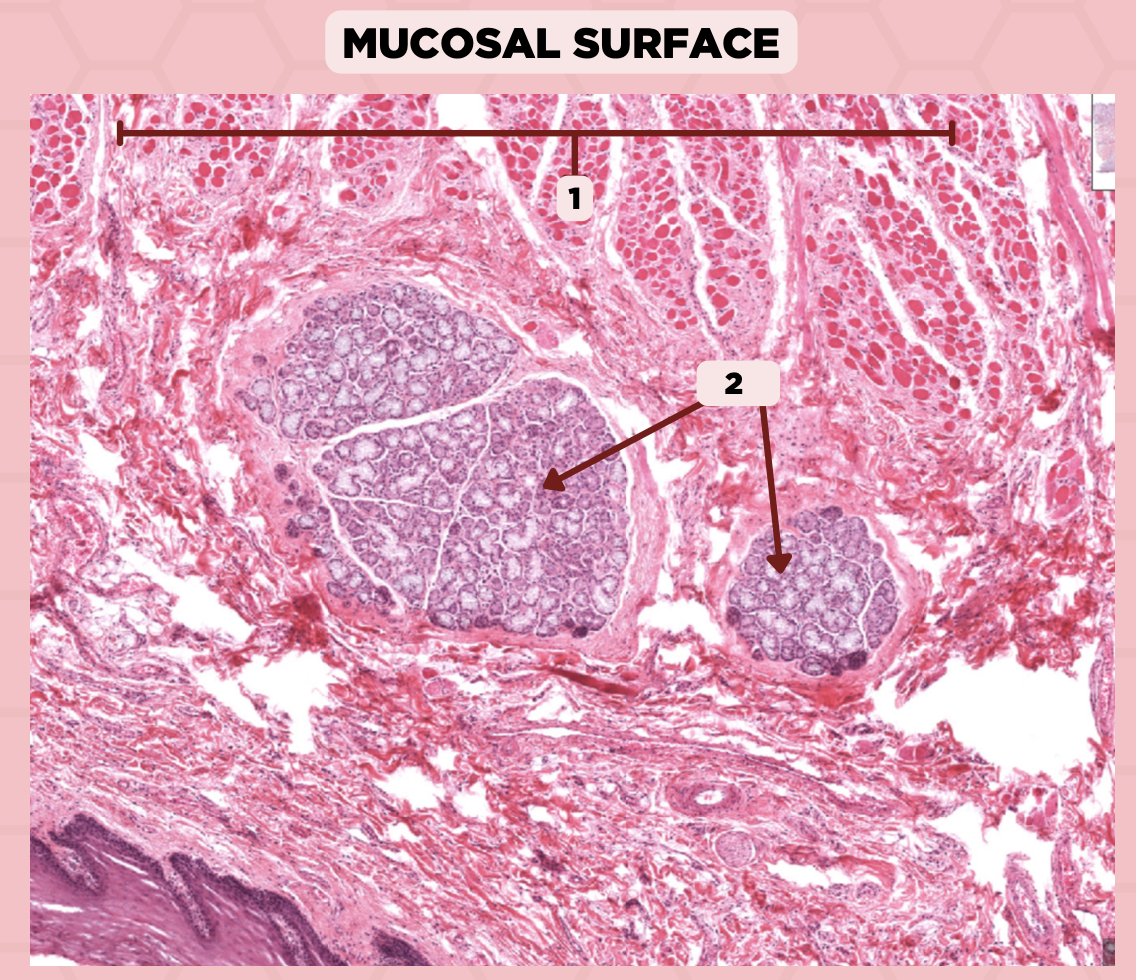

Lip

What specimen is showed in the picture?

Labial Glands (in the Mucosa)

Identify the structure labeled as 1.

Skeletal Muscle Cells

Identify the structure labeled as 2.

Lamina Propria

Identify the structure labeled as 3.

Mucosa

Identify the structure labeled as 4.

Lip

What specimen is showed in the picture?

Skeletal Muscle Fibers

Identify the structure labeled as 1.

Labial Glands

Identify the structure labeled as 2.